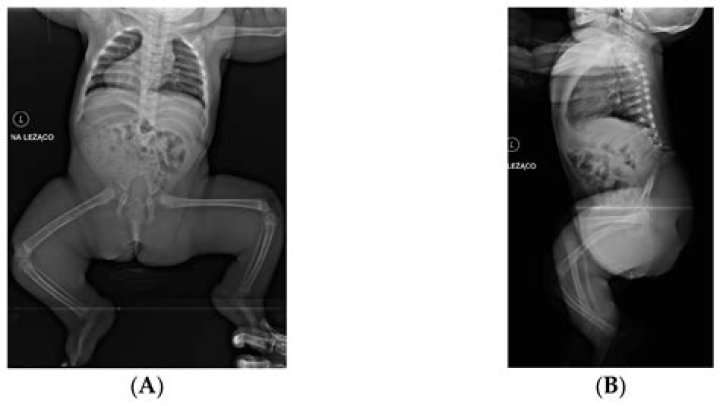

Zion Clark Talks Anatomy and Walking With His Hands, This Is How Caudal Regression Syndrome Works

Zion Clark was born sans legs because of an uncommon sickness known as caudal relapse condition. Nonetheless, in the event that a man’s height not set in ...